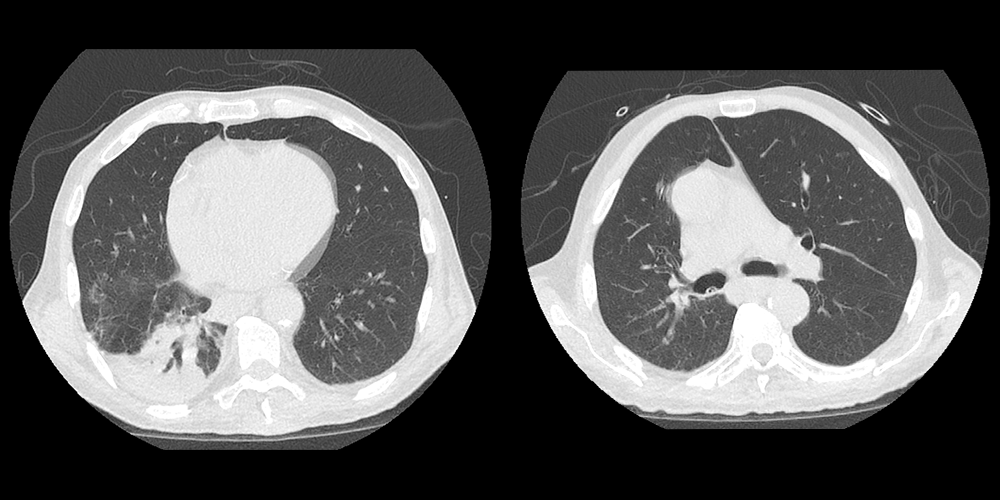

CT Chest – No IV Contrast

The patient has a consolidation in the dependent portion of the right lower lobe. There is also endobronchial debris in the right main bronchus. This is most consistent with aspiration pneumonia, which is more likely to affect the right lower lobe considering the more vertical course and larger caliber of the right main bronchus. A diagnosis of pulmonary embolism cannot be done with the current study considering the lack of IV contrast.

View the full study if you'd like to like a look yourself

2) Aspiration pneumonia often appears on imaging in the dependent portion of the right lower lobe considering the vertical course and larger caliber of the right main bronchus compared to the left main bronchus. Generally, they occur in the basilar portions of bilateral lower lobes in upright patients. In supine patients, often appear in the posterior segments of the upper lobes and the superior segments of the lower lobes.